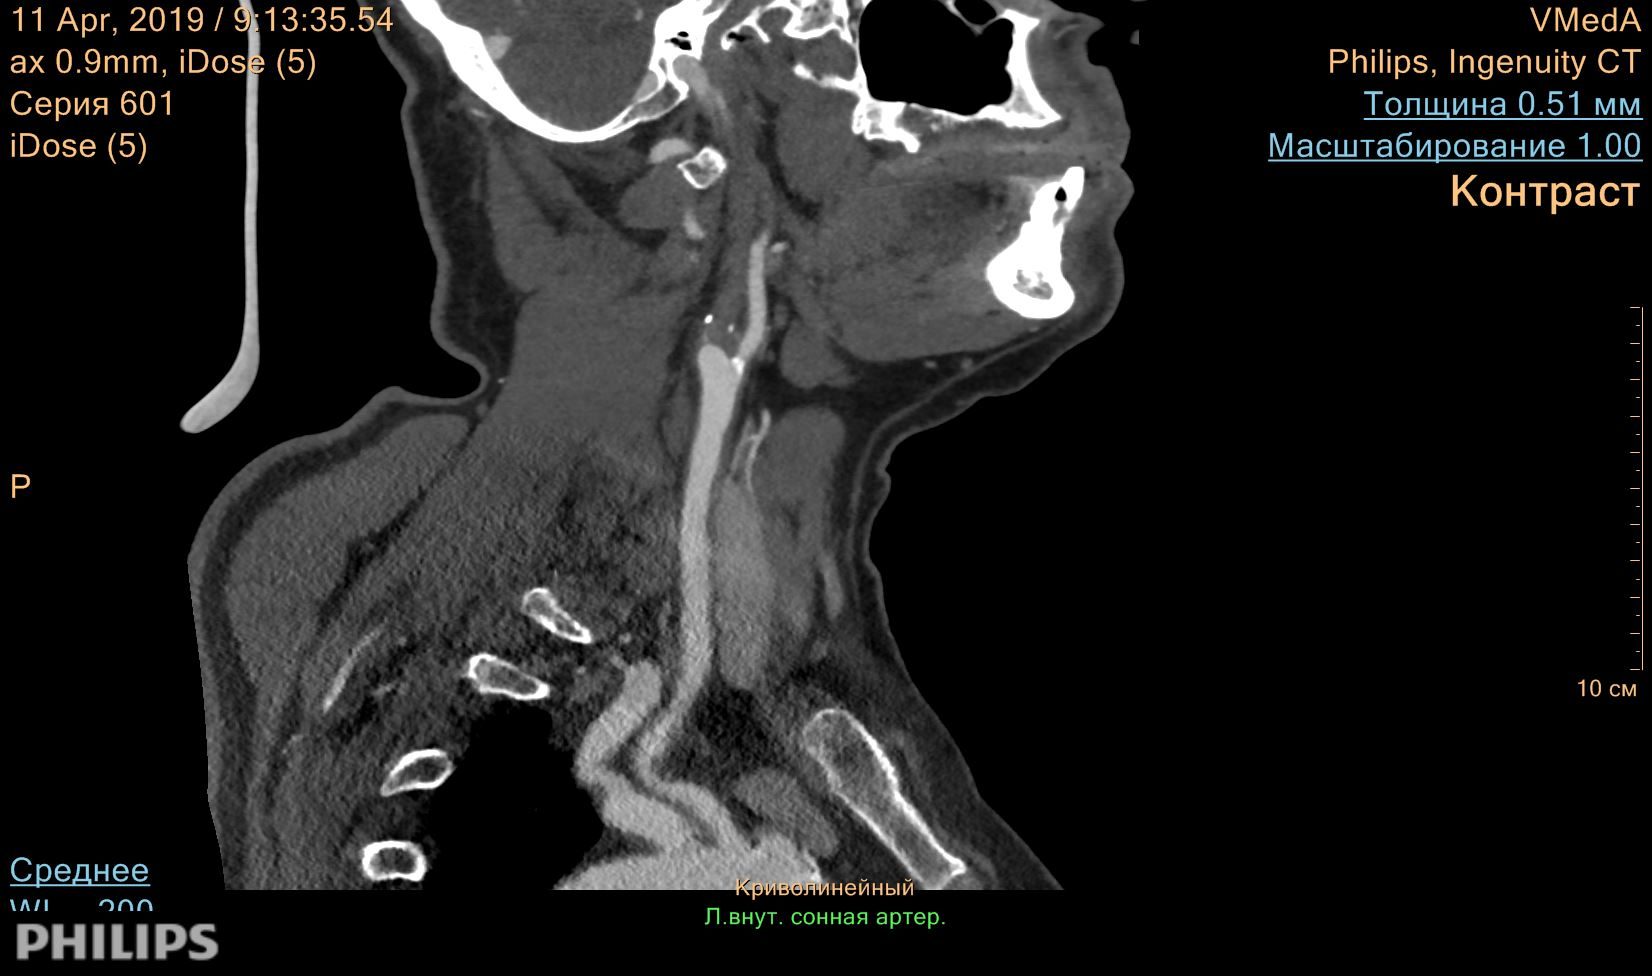

Результаты КТ-ангиографии: протяженная окклюзия левой внутренней сонной артерии, стеноз правой внутренней сонной артерии в приустьевом отделе на 40% по диаметру по ECST и на 20% по диаметру по NASCET.

Рис. 3. КТ-ангиография сосудов головы и шеи, криволинейная реконструкция.

Окклюзия левой внутренней сонной артерии в приустьевом отделе.